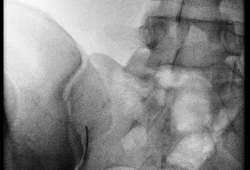

Op de recovery wordt er voor de behandeling een infuus geplaatst. Eénmaal in de behandelzaal neemt u op de buik plaats op de behandeltafel. Na ontsmetting van de huid wordt het gewricht onder begeleiding van röntgendoorlichting of echografie aangeprikt met een fijn naaldje. De huid wordt eerst lokaal verdoofd. Daarna wordt contraststof ingespoten om de juiste positie te controleren, gevolgd door een mengsel van verdoving en een ontstekingsremmer (corticosteroïd).